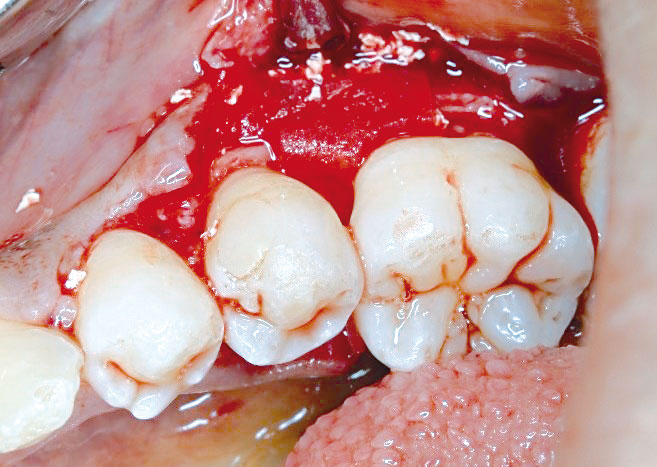

02/08 - Raised flap showing the defectRegeneration at LR6 with cerabone® and collprotect® membrane using simple papilla preservation technique - Dr. D. Chatzopoulou